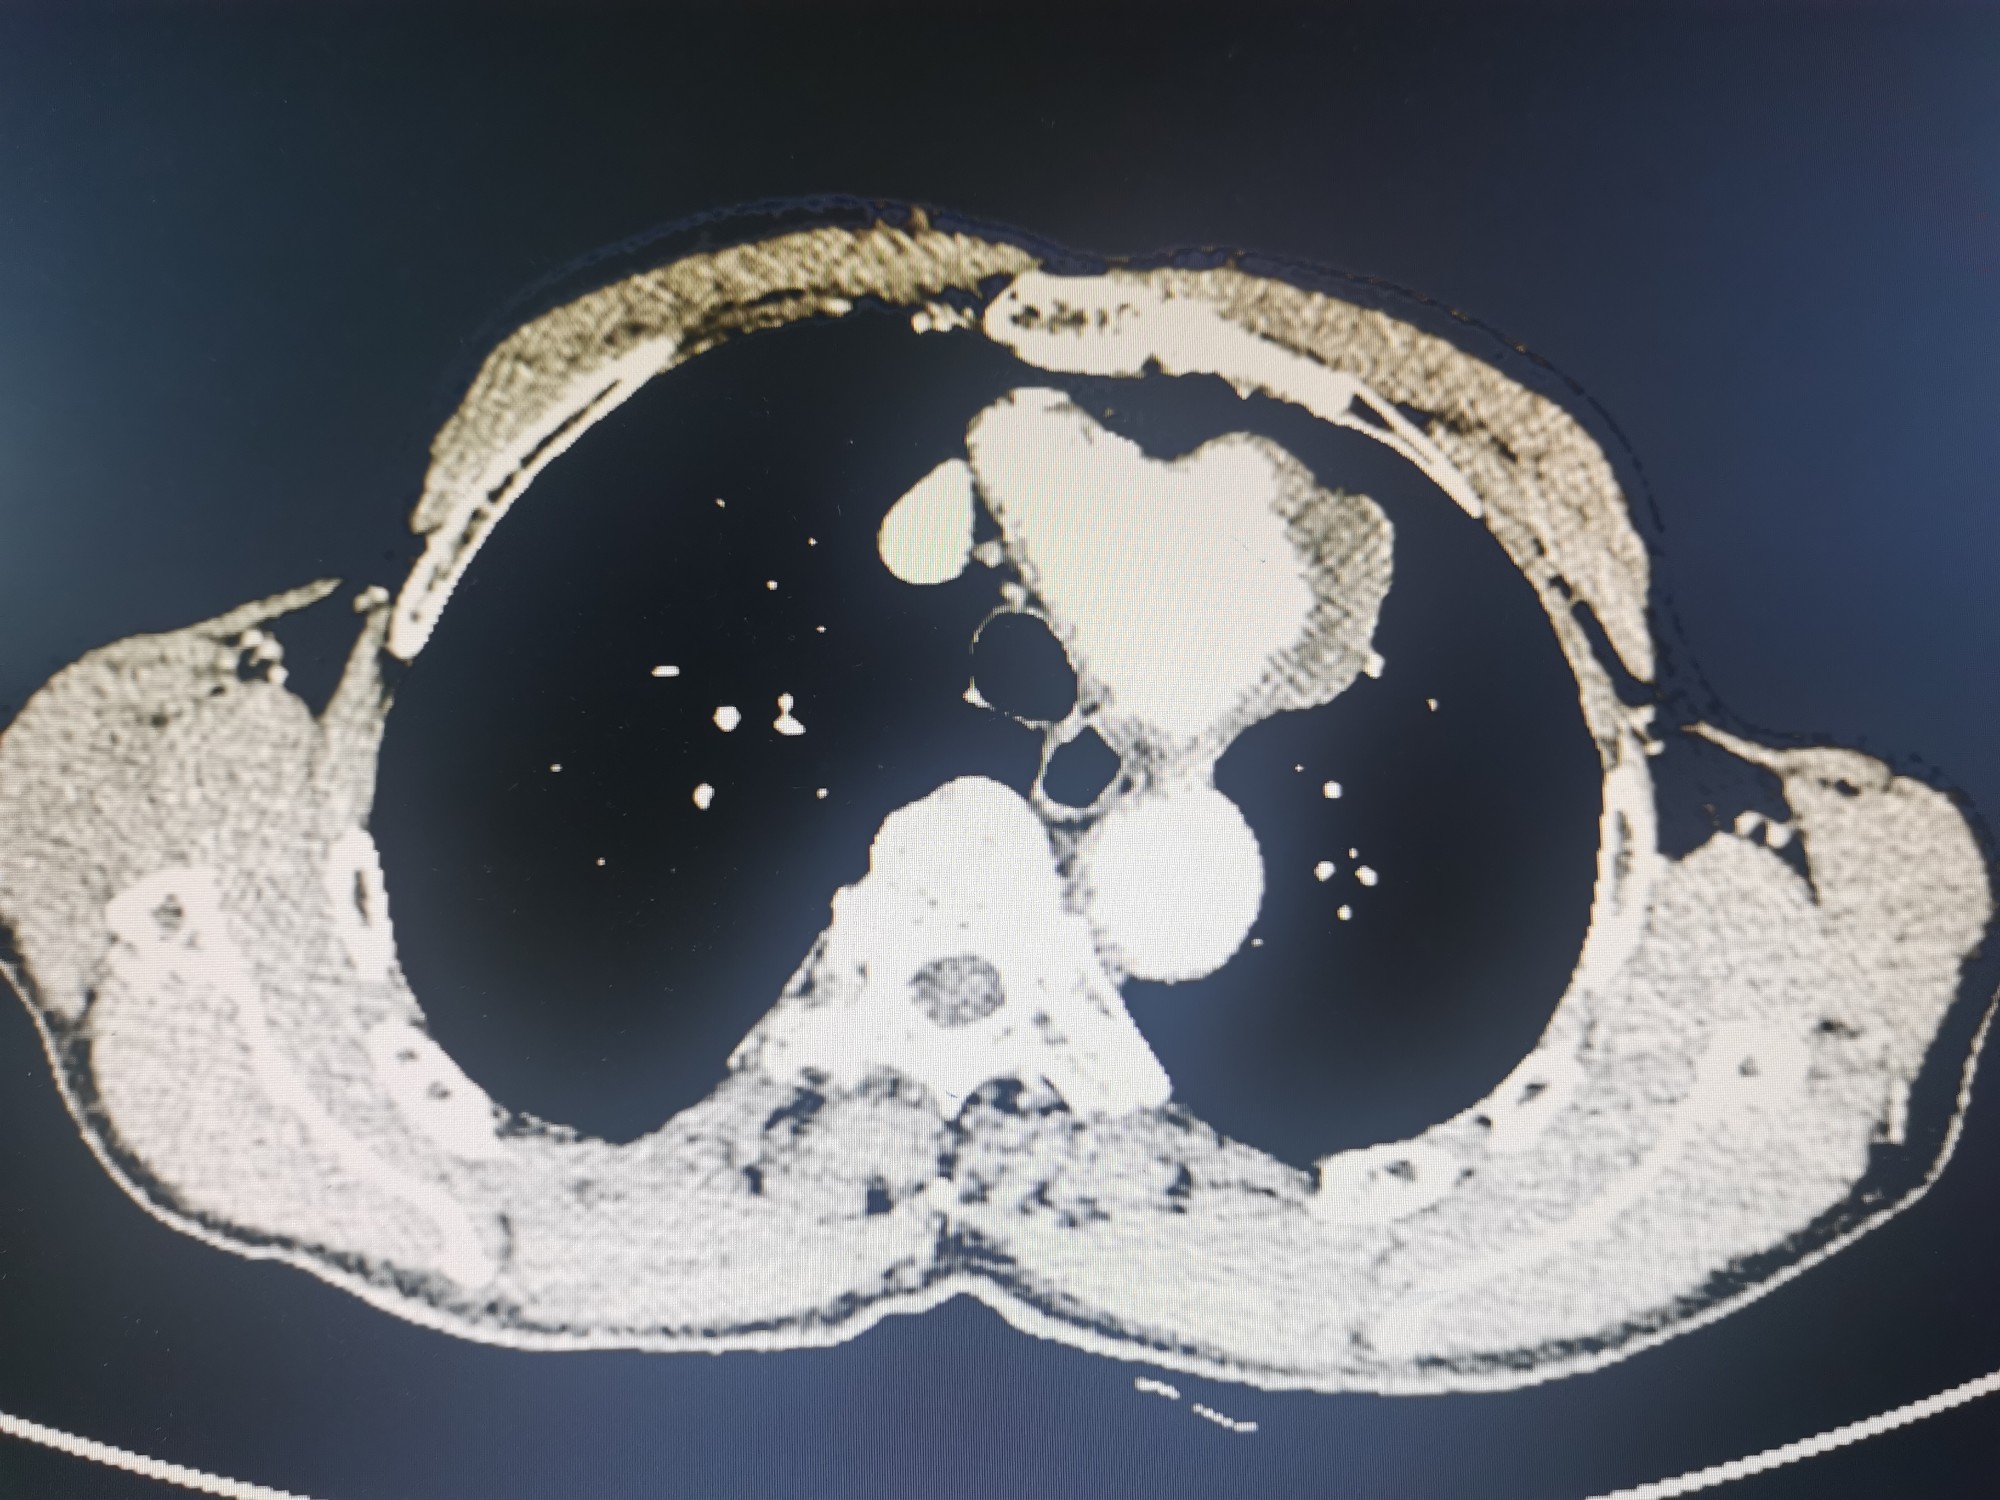

术前CTA